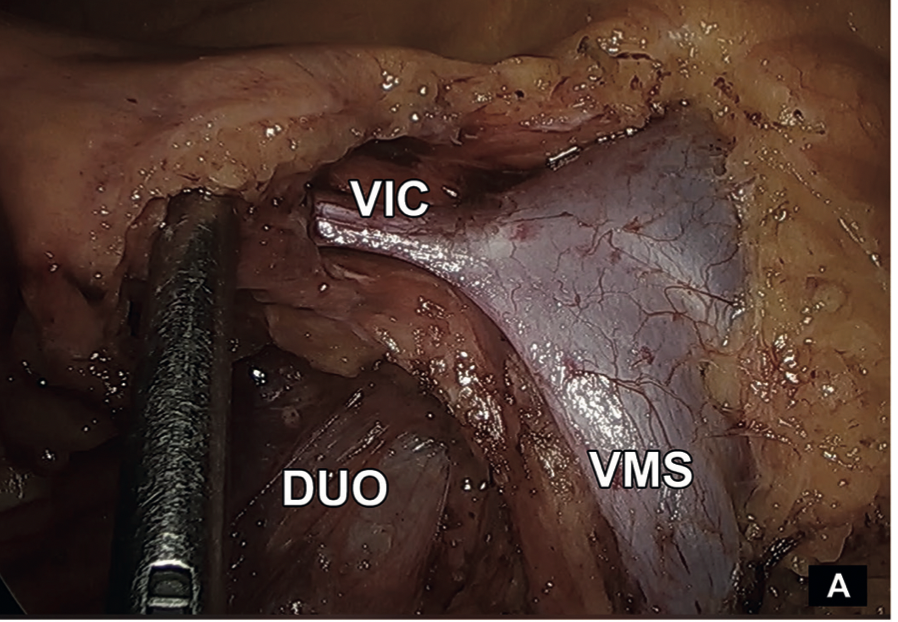

Caterina Contreras Bertolo, Javier Vela Ulloa, Felipe Bellolio Roth

|

|

|